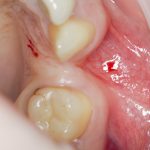

Теперь возьмём клинический случай (нижняя челюсть, отсутствия 35, 36, 37 зубов, атрофия альвеолярного гребня по ширине):

и рассмотрим его через парадигму методологического редукционизма. Или, если хотите, сквозь Бритву Оккама.

Мы имеем относительно небольшой дефект, не позволяющий, однако, установить имплантаты правильного размера в правильное положение. И два варианта остеопластической операции, НКР и АТККФ.